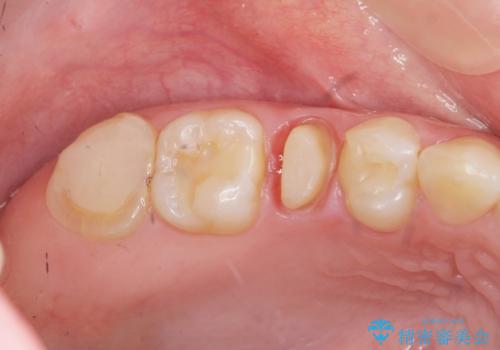

エナメル質・象牙質に限局する虫歯 →インレー修復

歯の神経に達する虫歯 →根管治療 クラウン補綴

- 44万円 (セラミックインレー×2 ジルコニアクラウン×2)費用は治療当時の料金となります

症状に応じて適切な処置を行ったことで、抜歯を回避し良好な結果を得ることができました。